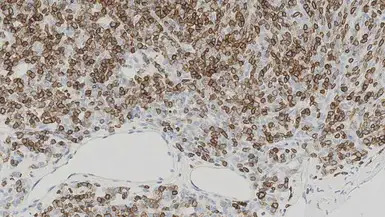

IHC-P analysis of human thymoma tissue using GTX01899 CD1a antibody [MTB1]. Note the neoplastic cells show a moderate to strong and distinct membrane staining reaction.